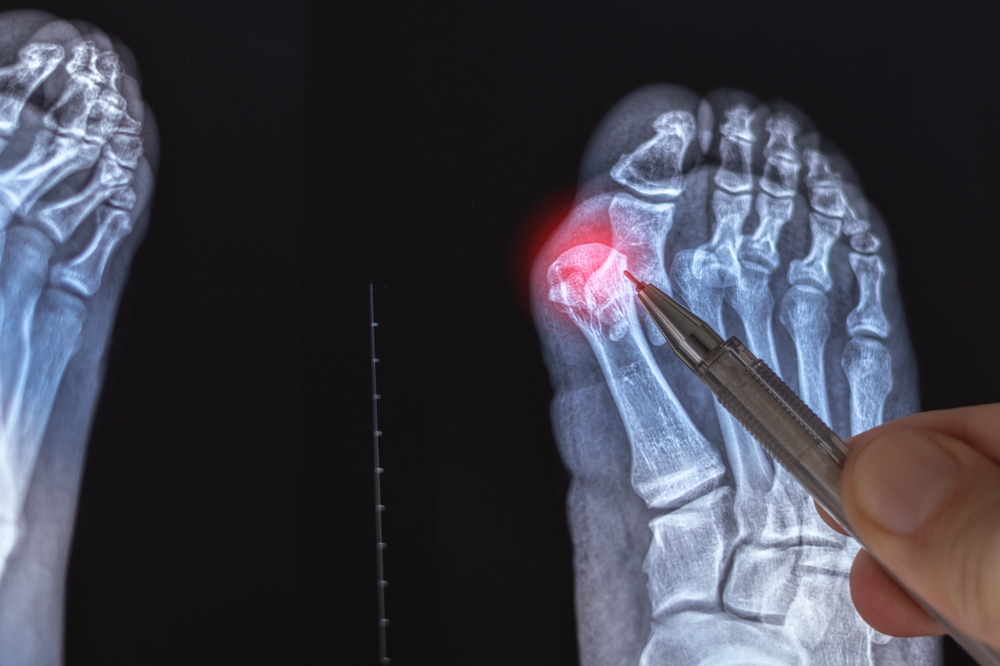

Suffering from foot pain? Discover the pros and cons of minimally invasive bunion surgery and see if this revolutionary 2026...